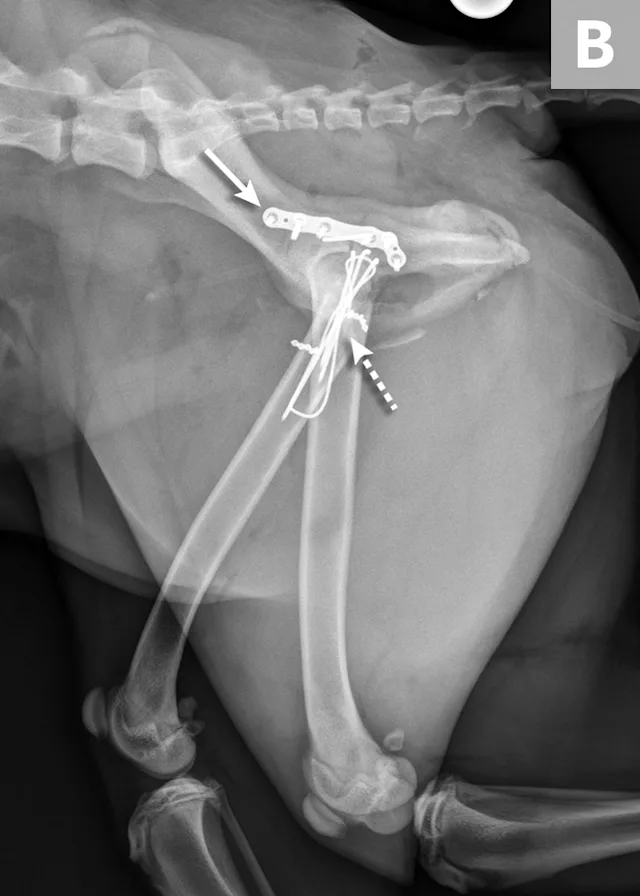

FIGURE 4A

Postoperative ventrodorsal (A) and lateral (B) projection images of the same dog in Figure 2. Fracture reduction was achieved with cross pins and a figure-eight hemicerclage wire (black arrows). Reduction was protected via application of a locking string-of-pearls neutralization plate (solid white arrows). To gain access to the full extent of the fracture, a greater trochanteric osteotomy was performed and stabilized with a positional screw and pin (dashed arrows). The ventrodorsal postoperative radiograph revealed a sacral fracture not previously appreciated (arrowhead). The fracture was successfully treated with conservative management.